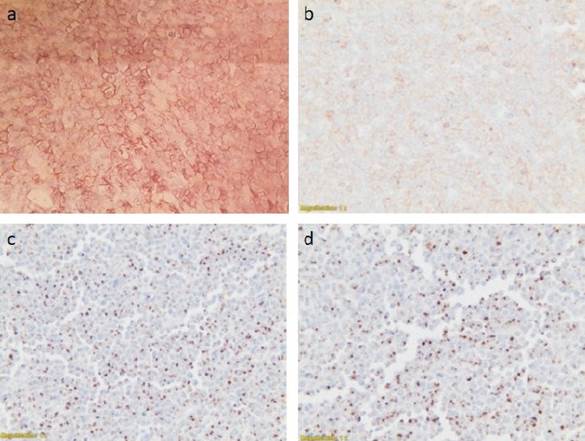

El análisis histopatológico de la masa la identificó como un linfoma no Hodgkin extranodal a células T/NK (natural killer) de tipo nasal (figura 4).

Figura 4: Biopsia pericárdica y análisis inmuno-histoquímico. a) Intenso marcado ACL (CD45RO), >90%. b) Intenso marcado CD8+. c) Marcado focal de CD56 con intensa expresión de gránulos citotóxicos de granzima B. d) Marcado TIA-1. Compatible con linfoma extranodal tipo nasal a células T/NK.